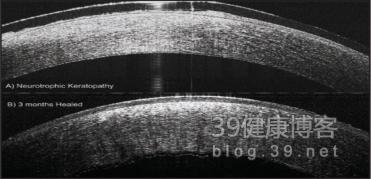

图22 未愈合的神经营养性上皮缺损(A)和经过配戴接触镜点滴自体血清3个月后上皮愈合(B)(2)。